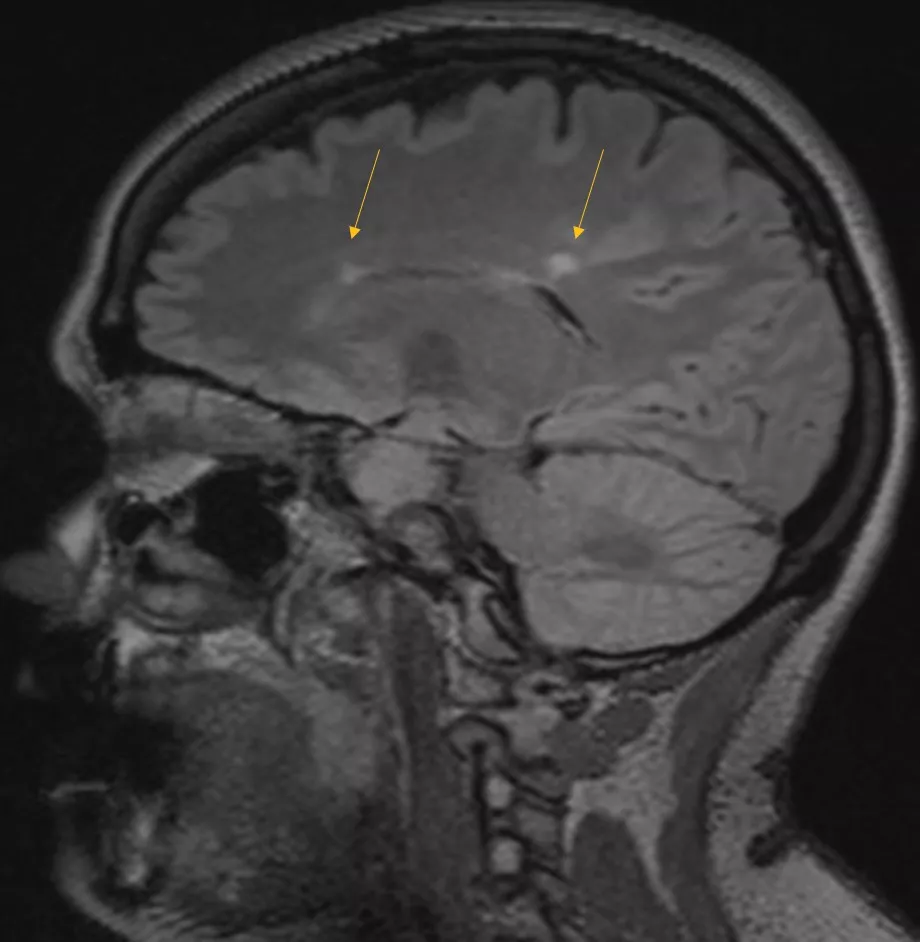

2021 Brain MRI

She had an actively enhancing juxtacortical lesion present in the left temporal region.

Mizell - MS 3-6